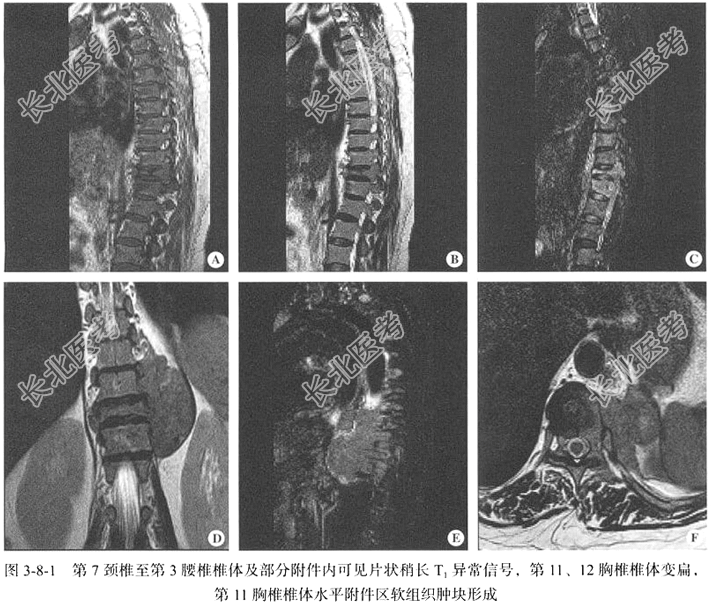

【胸椎MRI检查】仰卧位,以矢状位扫描为主,包括T₁WI、T₂WI及T₂WI脂肪抑制序列,扫描范围自第7颈椎至第1胸椎;辅以冠状位、轴位T₂WI序列。

【影像图片】见图3-8-1。

【手术所见】患者取俯卧位,C臂下定位第11胸椎椎体后,常规消毒铺巾。在第11胸椎椎体水平背部偏左侧皮肤切一小口,长约0.5cm。用穿刺套管针经皮穿越椎弓根至椎体内。在C臂下行正侧位透视观察,位置良好,拔出套管针芯后,插入环钻取出病变区域组织2块送病检,术毕,切口贴敷料。肉眼所见:骨髓条索状物3条,长0.2~0.4cm,直径0.2cm,呈灰白色,质中。

【病理所见】胸椎病变,破碎骨组织2块,于骨组织周边见少许小至中等大小的细胞,骨髓常规:增生活跃,骨髓瘤细胞占52%,双核、三核及多核瘤细胞易见,考虑为多发性骨髓瘤。骨髓活检:HE及PAS染色示骨髓增生较活跃(60%~70%),异型浆细胞明显增生(约80%),肿瘤细胞呈浆细胞样分化,细胞单一,胞质丰富,排列密集,弥漫分布,可见核仁(图3-8-2);偏成熟阶段粒红系细胞散在分布。网状纤维染色(MF0级)。免疫组化标记结果显示浆细胞分化,结合形态学与免疫组化结果诊断为浆细胞性骨髓瘤,κ链限制性表达。免疫组化结果:MPO粒系(+)、CD235a红系(-)、CD61巨核系(+)、CD38(-)、CD138(+)、κ(+)、λ(-)、CD117(-)、CD34(-)、CD3(-)、CD20(散在+)。

【病理诊断】浆细胞性骨髓瘤。